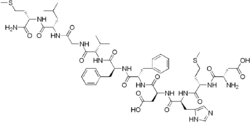

Synthesis

Neurokinin B is found in humans as a ten-peptide chain (decapeptide) attached to a terminal amide group. The peptide formula is H-Asp-Met-His-Asp-Phe-Phe-Val-Gly-Leu-Met-NH2 (DMHDFFVGLM-NH2).[5] Neurokinin B (NKB), is encoded by the TAC3 gene in humans and Tac2 in rodent species.[6] Neurokinin B is expressed along with the peptides kisspeptin and dynorphin A in the neuronal cells of the arcuate nucleus.[6] Five exon segments in the TAC3 gene encode for the NKB precursor known as preprotachykinin B. Preprotachykinin B is then proteolytically cleaved into the pro-peptide proneurokinin B. A second proteolytic cleavage of proneurokinin B produces the final product neurokinin B.[6]